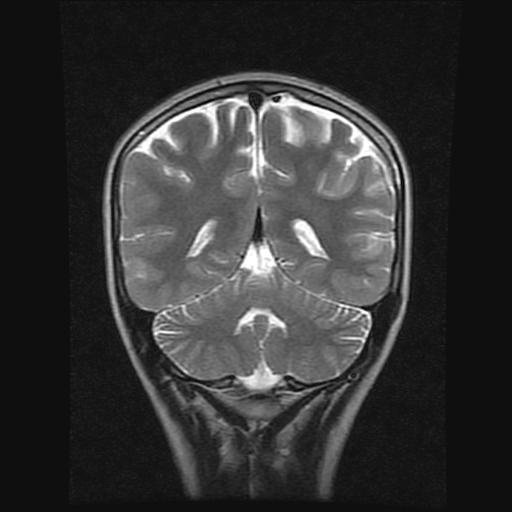

9岁女孩,三岁时诊断为癫痫,一直服丙戊酸钠,现患者一般情况良好,家长复查核磁片,看能否停药..

巨脑回